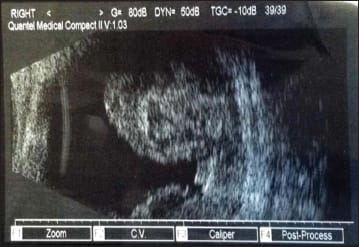

The patient called and was examined two days later due to intractable nausea and vomiting. His vision at this visit was barely light perception. The IOP in the right eye was 37 mm Hg by applanation. The choroidal hemorrhages were worse on examination and on ultrasonography (Figure 2). The anterior chamber was shallowing as well.

Figure 2. Two days later, the choroidal hemorrhages were worse on examination and on ultrasonography.